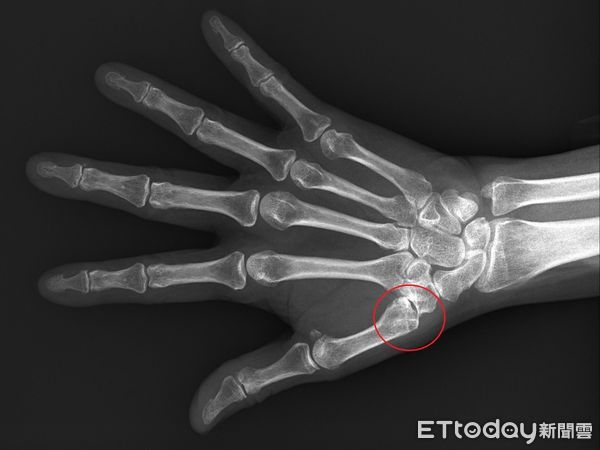

▲拇指無力要當心是否關節已鬆脫。(圖/台北慈濟醫院提供)

周博智說明,臨床會以X光判斷關節磨損程度,若程度尚輕,可以用貼紮或護腕固定,加上止痛藥物控制,但在這樣的保守治療下仍然影響生活工作機能,另現在也有新式微創手術進行治療,先在手腕開0.5~1公分的入口,再將滑脫關節矯正至關節軸心,而後將可吸收的螺釘固定在第二掌骨基部,以第二掌骨基部借力使力,就可以分攤拇指基部的受力,而且不會犧牲拇指的靈活度。